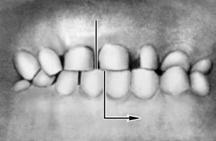

Рис. 6. Схематическое изображение челюстей при сагиттальных аномалиях прикуса, по классификации Энгла: а — аномалии первого класса; б — аномалии второго класса, первого подкласса; в — аномалии второго класса, второго подкласса; г — аномалии третьего класса; вертикальными линиями указано соотношение верхнего и нижнего первых моляров.

|